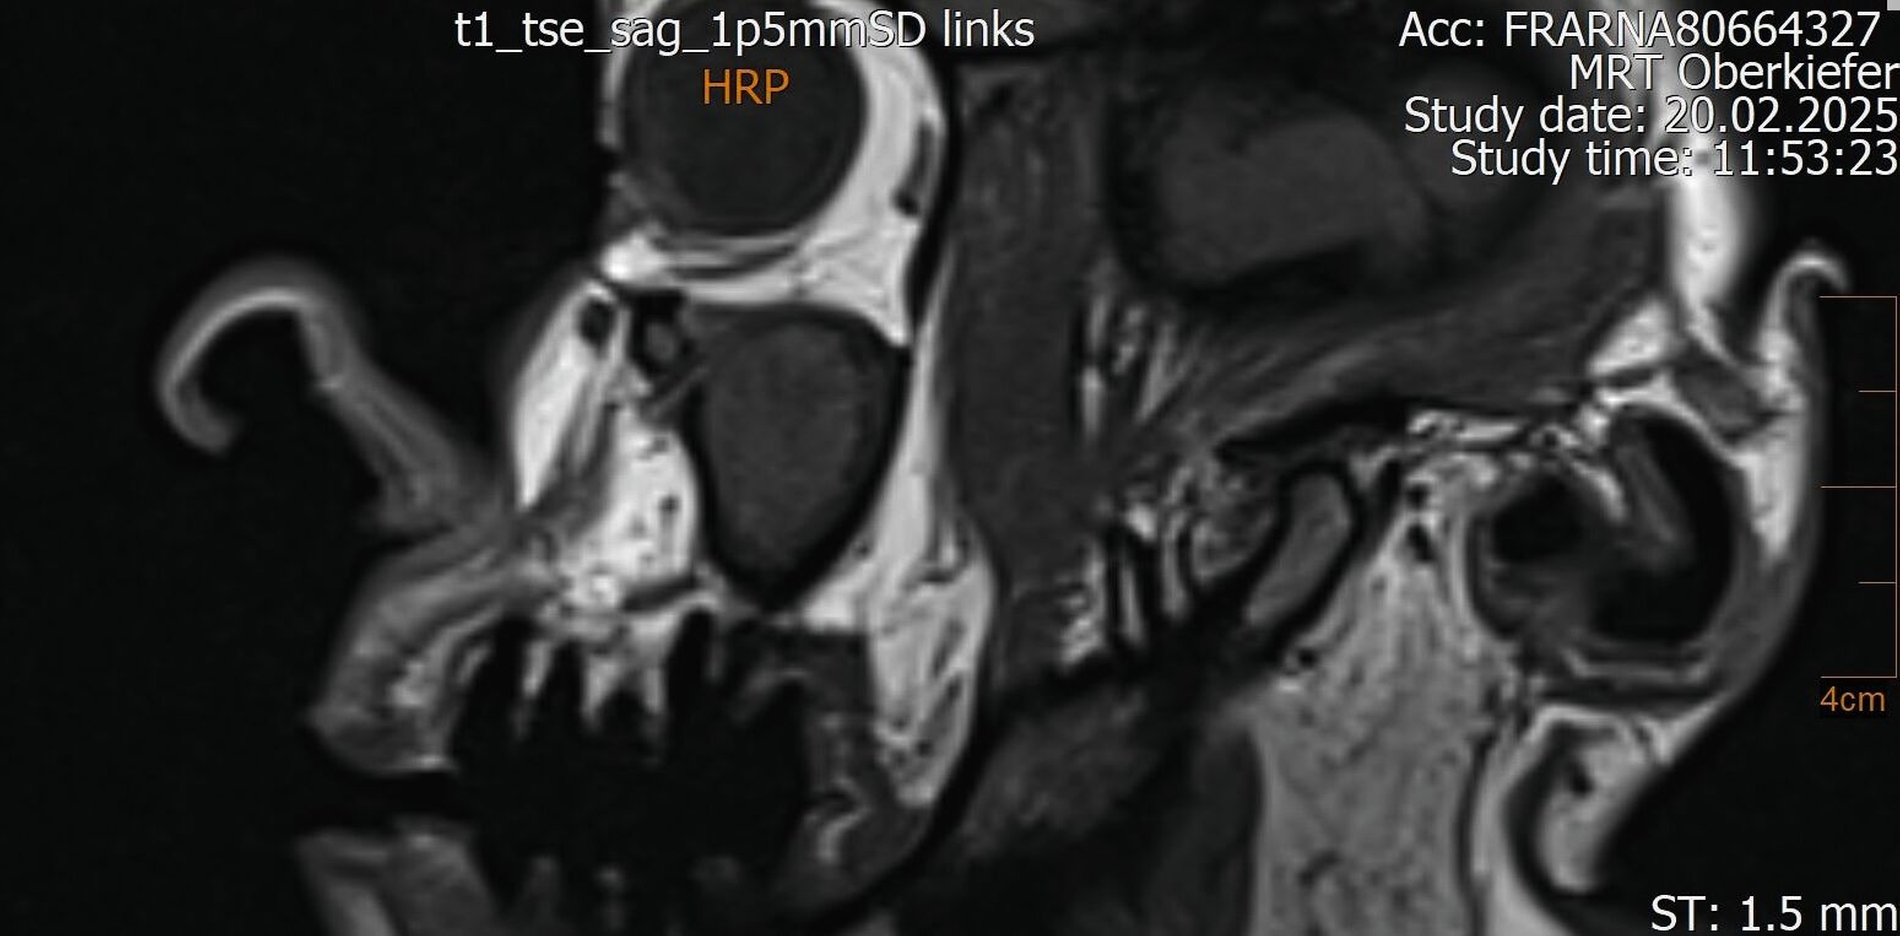

Der Wendepunkt erfolgte schließlich im Februar 2025 im Rahmen einer Kontrolluntersuchung bei der Hauszahnärztin. Diese nahm die langjährige Beschwerdesymptomatik ernst und veranlasste eine MRT-Untersuchung am Deutschen Zentrum für Dentaldiagnostik (DZD). Die MRT-Bildgebung ergab eine chronische Osteomyelitis im Bereich der Extraktionsregion von Zahn 27 sowie eine ausgeprägte apikale Ostitis an Zahn 26 mit vollständiger Verschattung der linken Kieferhöhle und Ausdehnung der Entzündung ins Siebbein und in die Stirnhöhle. Auch konnte durch den befundenden Radiologen eine interradikuläre Fistelung an Zahn 26 erkannt werden, weshalb die Sinusitis als odontogen eingestuft wurde (Abbildungen 4 bis 7).

In speziellen Fällen kann ergänzend eine MRT sinnvoll sein – etwa bei unklarer Symptomatik, bei Verdacht auf Weichteilbeteiligung, bei einem chronisch-rezidivierenden Verlauf oder bei unzureichender Abgrenzbarkeit im DVT. Im vorgestellten Fall ermöglichte die MRT den Nachweis des interradikulären Fistelgangs zur Kieferhöhle und damit die korrekte Zuordnung des Entzündungsfokus.